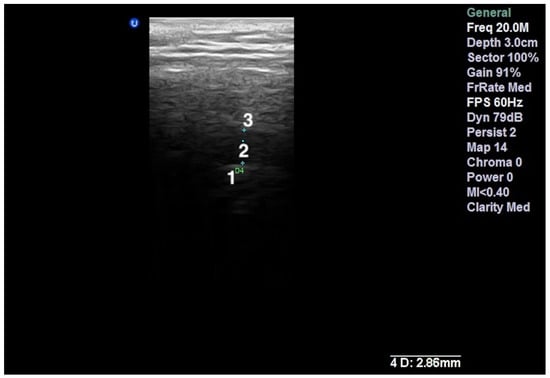

- Talmaceanu, D.; Lenghel, L.M.; Bolog, N.; Stanila, R.P.; Buduru, S.; Leucuta, D.C.; Rotar, H.; Baciut, M.; Baciut, G. High-resolution ultrasonography in assessing temporomandibular joint disc position. Med. Ultrason. 2018, 20, 64–70. [Google Scholar] [CrossRef] [Green Version]

- Talmaceanu, D.; Lenghel, L.M.; Bolog, N.; Buduru, S.; Leucuta, D.; Horatiu, R. High-resolution ultrasound imaging compared to magnetic resonance imaging for temporomandibular joint disorders: An in vivo study. Eur. J. Radiol. 2020, 132, 109921. [Google Scholar] [CrossRef]